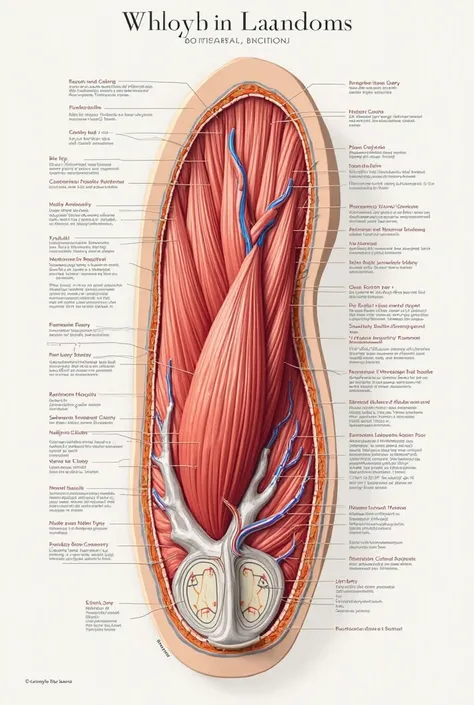

A diagram of the anatomy of the human body

Realice un dibujo de la piel. Coloque las siguientes referencias: Epidermis Fermis Hypodermis Keratinized squamous stratified epithelium Hair Sebaceous gland Sweat gland Pilo erector muscle Connective tissue Blood vessels Nerves Adipocytes

Coloque las siguientes referencias:

Epidermis Fermis Hypodermis Keratinized squamous stratified epithelium Hair Sebaceous gland Sweat gland Pilo erector muscle Connective tissue Blood vessels Nerves Adipocytes